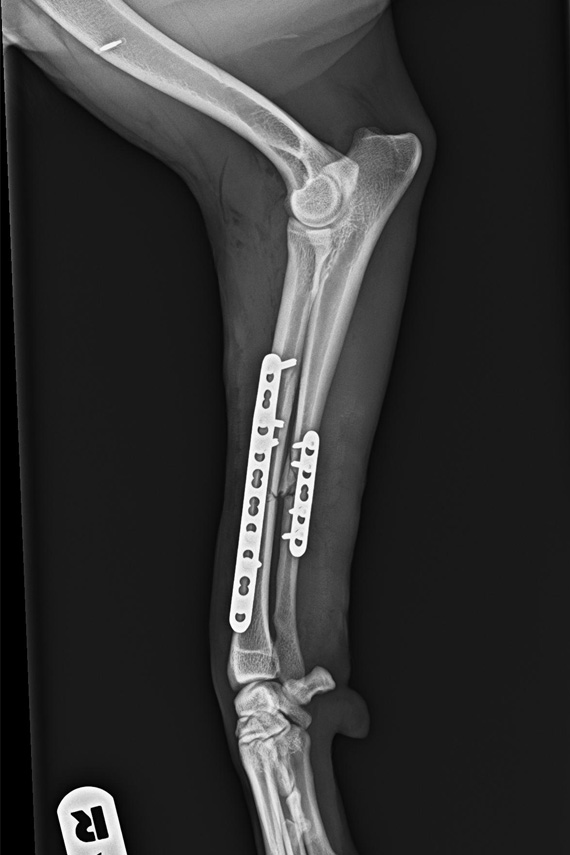

Radius Ulna Querfraktur Hund

Radius Ulna Querfraktur bei einem Hund

Versorgung Radius Ulna Fraktur

Radius und Ulna wurden jeweils mit einer eigenen Platte verplattet.

Ulna Fixateur post-op

Diese Versorgung empfiehlt sich bei größeren und aktiven Hunden.